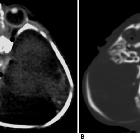

- thoracopagus: thorax, commonest site (~70% )

Radiographic assessment

The prognosis for conjoined twins, in general, is quite poor. Approximately 40-60% of conjoined twins are stillborn and almost 35% of live births do not survive beyond 24 hours. Of those who do survive, surgical separation is sometimes possible (but with higher failure rates if performed within the first 3 weeks ). Surgical separation, in general, is in most cases very challenging with high mortality, depending on the complexity of shared structures. Of those with thoracopagus, ~75% have extensively joined hearts which in turn preclude a successful separation.